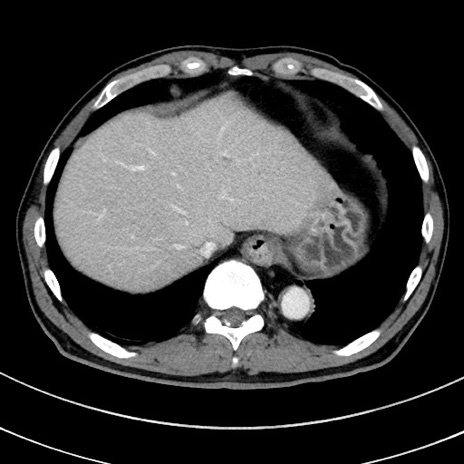

症例8(横断像)

【症例】 60歳代男性

【主訴】 黒色吐物

【現病歴】 4日前から嘔気自覚、2日前の朝食後にも嘔気あり、自分で手で嘔吐反射起こし嘔吐したところ血が混ざっていたため受診。

【既往歴】 5年前汎発性腹膜炎を伴う急性虫垂炎で手術、高血圧、前立腺肥大症、高脂血症

【身体所見】 腹部正中に手術癩痕あり 腹部平坦・軟圧痛なし膨満感あり

【データ】WBC 8400、CRP 4.54